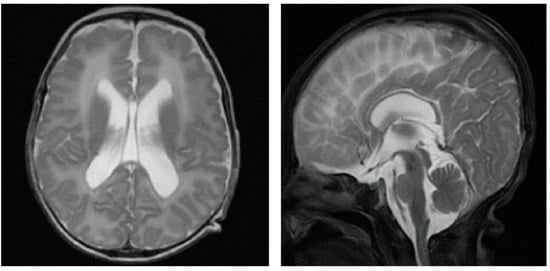

2.3. Accessory Examination

| Central nervous system abnormalities | Ventricular dilatation, hypoplasia, agenesis of the corpus callosum, mega cisterna magna |